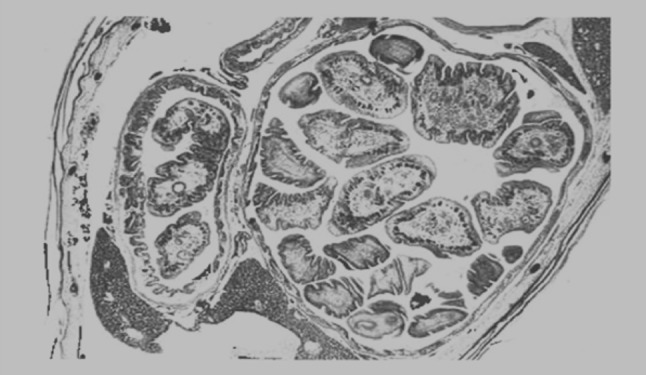

Fig. 6.

Transverse section of common carp showing attenuation of the gut and partial occlusion from tapeworms within

The pathological changes caused by the strobila of B. acheilognathi generally exceed those associated with scolex attachment. The extent and severity of this damage can vary depending on host size, parasite size and intensity of infection (Davydov 1978; Hoole and Nisan 1994). In small cyprinid fish, pathological changes are characterized by distension of the intestine, compression of the intestinal folds and pronounced thinning of the gut wall (Fig. 6). In very heavy infections severe distension may be accompanied by a complete loss of normal gut architecture, with occlusion of the intestine, congestion, compression, pressure necrosis, thinning and atrophy of the mucosa (Nakajima and Egusa 1974a) (Fig. 6). Separation and degeneration of the epithelium, with regions of complete epithelial loss can occur. Lysis of large areas of the mucosa with necrotic changes has also been observed in heavily infected carp fry (Davydov 1977; Sekretaryuk 1983). The presence of parasite eggs caught between the parasites and gut wall can lead to epithelial abrasion, exfoliation of host cells and indentation of the mucosa. This damage, combined with an already compressed gut wall, can lead to ulceration. Inflammatory changes may be pronounced during heavy tapeworm burdens, with increased numbers of lymphocytes and eosinophilic granular cells occurring throughout infected regions. Paradoxically, heavy parasite infections and marked pathological changes have been observed in apparently healthy fish (C. Williams, unpublished data). Nakajima and Egusa (1974a) described no signs of mortality, despite serious histopathological changes in common carp fry. What is seldom clear in these cases are the metabolic and physiological costs of these infections and the energetic or behavioral demands upon infected fish to maintain condition.